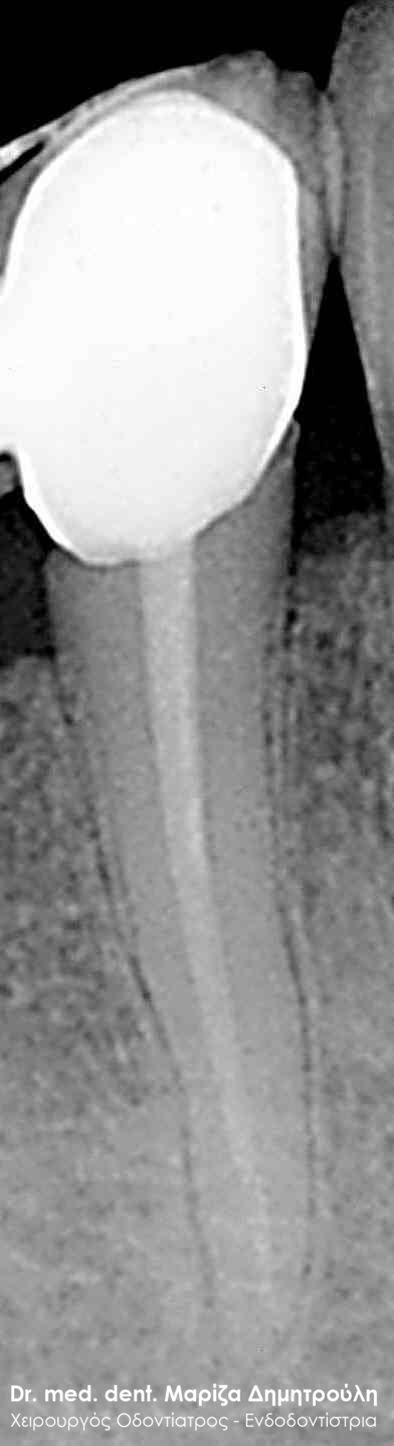

Root canal retreatment

BEFORE